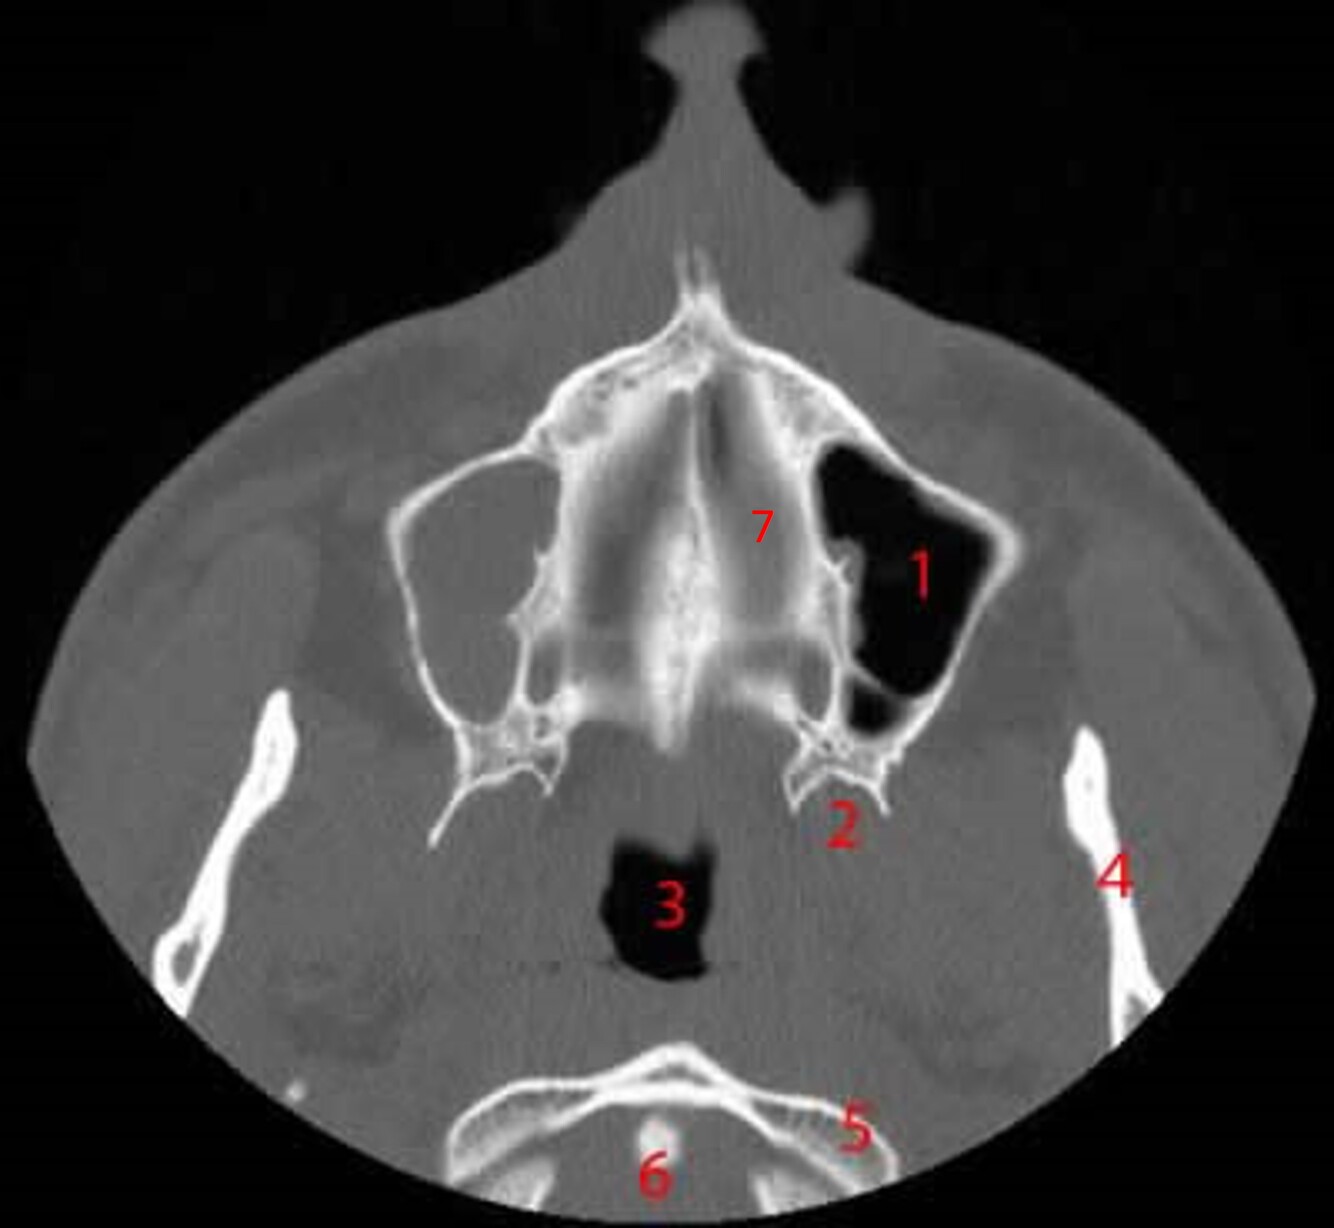

21

Label 1-9

A

1=Lt uncinate process

2=Lt infundibulum

3=Lt hiatus semilunaris

4=Lt ostium (mandible)

5=Lt middle nasal meatus

6=Lt maxillary sinus

7=Lt Zygoma

8=Lt medial rectus muscle

9=Rt globe of eye